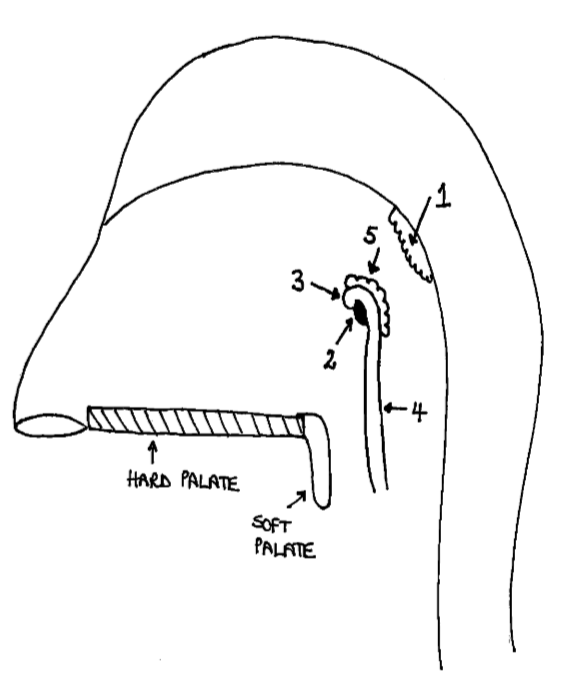

What is the anterior wall of 1?

posterior nasal choanae

What is the roof of 1?

body of sphenoid and basilar part of occipital

What is the posterior wall of 1?

anterior arch of atlas covered in pharyngobasilar fascia

What is the floor of 1?

soft palate

What is 1?

pharyngeal tonsil

What is 2?

pharyngeal opening of pharyngotympanic tube

What is 3?

tubal elevation

What is 4?

salpingopharyngeal fold

What is 5?

tubal tonsil